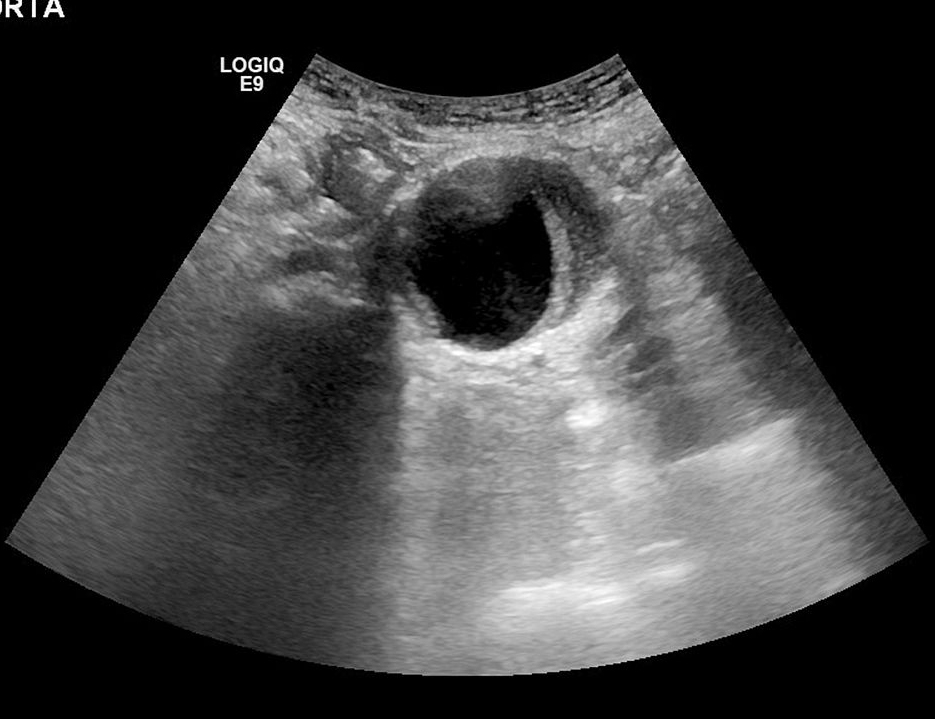

4. 4. 1 彩色多普勒超声 超声的特点是无创、费用低廉、无辐射 , 而且数据可靠。彩色多普勒超声已经广泛应用于腹主动脉瘤的筛查、术前评估和术后随访 , 其敏感性可以达到 90% 以上。不足之处是对操作者依赖性强 , 探头不同切线会得到不同的数据 , 影响结果测量的客观性 ; 对于位置较深的腹主动脉瘤和髂动脉瘤 , 由于肠道气体干扰 , 其诊断准确率也会有所下降。